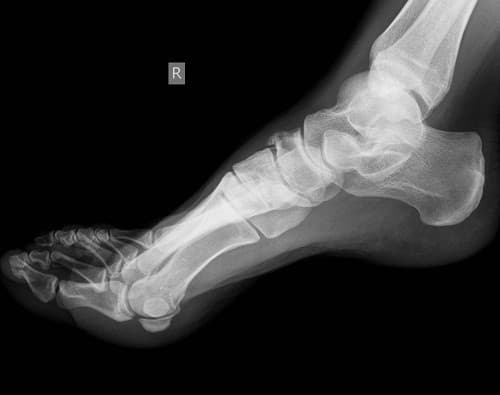

– Chụp X – quang: giúp phát hiện được hình ảnh lắng đọng tinh thể urate tại sụn khớp ở những cơn gút cấp đầu tiên hoặc ngay cả khi chưa có triệu chứng lâm sàng. Siêu âm có thể phát hiện sớm các biến đổi ở phần mềm, sụn khớp và xương do bệnh gút gây ra như hạt tôphi, hình ảnh khuyết xương, lắng đọng tinh thể urat trên bề mặt sụn khớp, tràn dịch khớp.

Chụp X – quang giúp phát hiện được hình ảnh lắng đọng tinh thể urate tại sụn khớp ở những cơn gút cấp đầu tiên hoặc ngay cả khi chưa có triệu chứng lâm sàng.